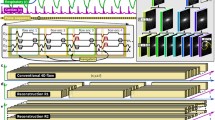

More recently, there has been expanding interest in applying artificial intelligence (AI), machine learning and deep learning methods to reconstruct higher-resolution cardiac cine MRI for a given acquisition time or to shorten acquisition time without degrading (or even improving) image quality from undersampled k-space. Such techniques use previous cardiac cine acquisitions (in the image or k-space domain) as training data to develop models for optimizing reconstruction on new cases (not part of the training data) [38,39,40]. In a small pilot study of adults, a deep learning algorithm was trained on fully sampled cardiac cine acquisitions and developed to optimize a parallel imaging reconstruction strategy known as ESPIRiT (eigenvalue-based iterative self-consistent parallel imaging reconstruction) [39,40,41,42]. The method was shown to outperform ESPIRiT combined with compressed sensing for overall image quality and accuracy of left ventricular segmentation when used in conjunction with a 12-fold accelerated bSSFP cardiac cine sequence [39, 41, 42]. A further enhanced version of this deep learning ESPIRiT technique used in combination with a 12-fold accelerated cardiac cine bSSFP sequence was later prospectively compared to conventional bSSFP with parallel imaging in a cohort of pediatric and young adult patients; the two protocols showed similar image quality and volumetry estimates despite substantial time-savings in the deep learning group (Fig. 5) [40]. Additional ongoing research centers on using deep learning to improve traditionally slow reconstruction times in non-Cartesian (e.g., radial) k-space cardiac cine sampling strategies, which otherwise offer shorter acquisition times and increased SNR [43, 44].

Utility of deep learning reconstruction for cardiac cine imaging, here in a 17-year-old girl with hypertrophic cardiomyopathy. a Short-axis end-diastolic conventional balanced steady-state free precession (bSSFP) image shows asymmetrical septal hypertrophy (arrow). LV left ventricle, RV right ventricle. b Short-axis free-breathing deep-learning-reconstructed and 12-fold-accelerated end-diastolic bSSFP image shows slightly less detail but adequate demonstration of the thickened septum (arrow) and ventricles. This is despite an almost 70% reduction in prescribed acquisition time, even without accounting for conventional cine breath-hold and recovery time

A general concern about deep learning reconstruction strategies is that they could produce unusual artifacts or images that obscure important pathology (potentially unbeknown to the interpreter), given that they are based on limited training data [45]. However, this phenomenon might be at least partially mitigated by using deep learning to optimize a k-space and physics-based algorithm with less dependency on the specific images used for training [40]. Nevertheless, while research efforts in deep learning–based reconstruction for cardiac cine imaging appear promising, practical vendor-based solutions are not available at the present time.